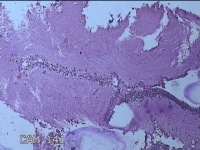

宫颈赘生物

性别

女

年龄

29岁

临床诊断

早期人工流产;宫颈赘生物

一般病史

人流见宫颈口有1赘生物。

标本名称

大体所见

灰白暗红色肿物1.3x0.8x0.3cm一个,表面糜烂。

图1